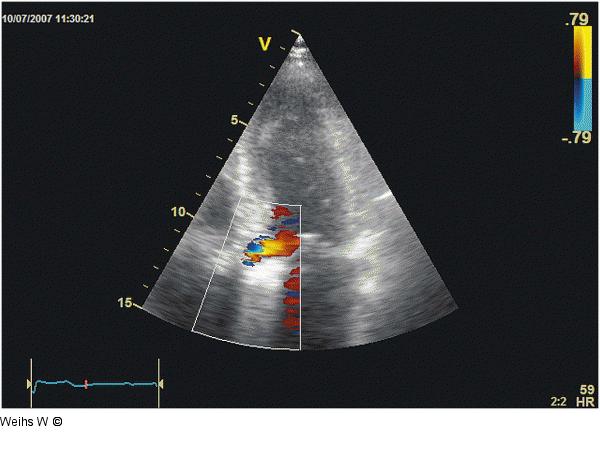

Abbildung 2: 5-Kammer-Blick Apikaler 5-Kammer-Blick. Mittelgradige gegen das Mitralsegel gerichtete Insuffizienz der Aortenklappenprothese, welche transvalvulär (und keinesfalls physiologisch) sein dürfte. |

Apikaler 5-Kammer-Blick. Mittelgradige gegen das Mitralsegel gerichtete Insuffizienz der Aortenklappenprothese, welche transvalvulär (und keinesfalls physiologisch) sein dürfte. |